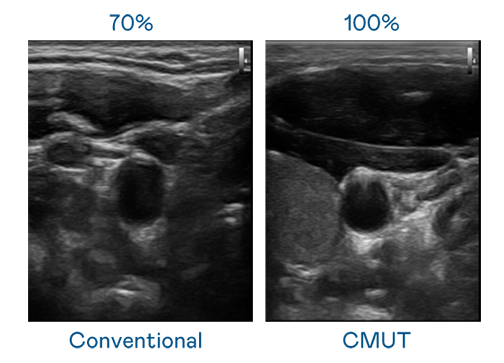

CMUT 技术是一种用电容式微机电元件来产生超音波讯号的技术。与传统 PZT 压电式技术相比,CMUT 频宽增加 30%,更宽频的超音波讯号让影像解析度大幅提升,是实现高影像品质医疗超音波扫描、促进精准医疗发展的关键技术。

超音波影像的解析度高低,首先取决于探头能发出的讯号频宽。9.1破解版 CMUT 可提供高清晰的超音波讯号,提供高频宽、高灵敏度、影像纹理细节更高的超音波影像,协助医护人员缩短影像判读时间及利用精准的医疗影像进行诊断。